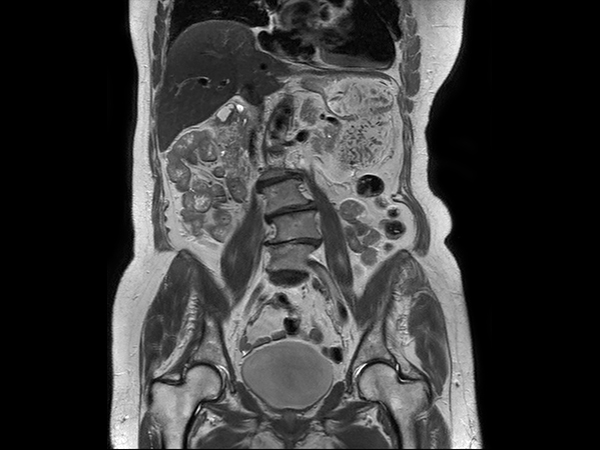

Coronal T2w SPAIR dS SENSE = 5, MobiView